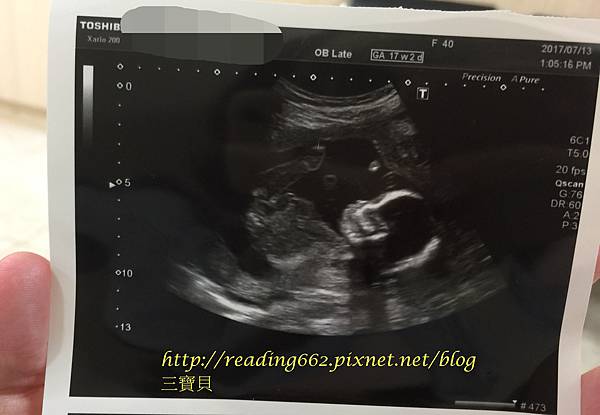

【意外之喜】 迎接生命中的三寶17W4D

這篇文章自上海回來發文後再次停頓了三個月之久,